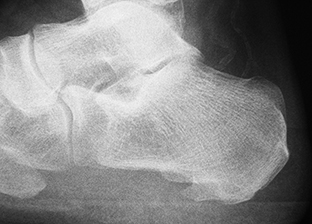

La apariencia anatómica es variable y se han clasificado en espolones sencillos e irregulares. El espolón sencillo es una estructura triangular que termina con una punta afilada, con una cortical ligeramente esclerótica y trabéculas bien desarrolladas. En contraste, los espolones irregulares tienen los bordes mal definidos y la trabeculación es poco clara y se producen cuando hay un fuerte proceso inflamatorio [52] (Figura 3).

Figura 3A

Figura 3B

Figura 3C

Figura 3. A, B, C) Imagen radiográfica de espolones del calcáneo.